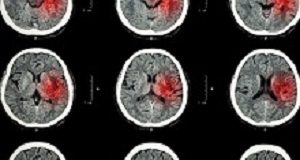

Home Tags Platelet-Oriented Inhibition in New TIA and minor ischemic stroke (POINT) trial

Tag: Platelet-Oriented Inhibition in New TIA and minor ischemic stroke (POINT) trial